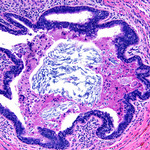

Microscopy image of non-necrotising granulomatous inflammation in the breast

From the collection of Liron Pantanowitz, MD, Tufts University School of Medicine, MA